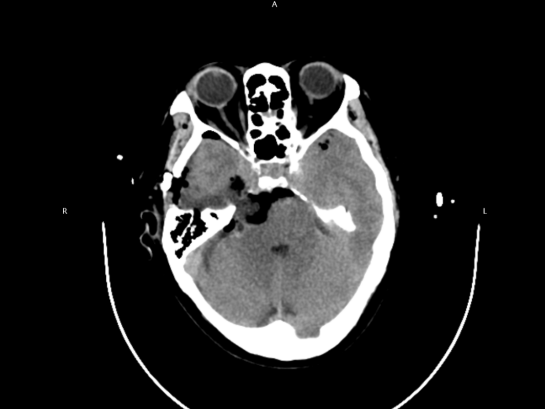

确定入院治疗后,黄光富教授既充分发挥自身专长,全程细致跟进住院事宜。在黄光富教授的带领下,神经外科团队成功为李阿婆实施了显微镜下三叉神经鞘膜瘤切除术,顺利切除这个被多家医院判定的 「高风险」 的肿瘤。患者后续恢复中,她的状态一天好过一天,最终顺利出院,与家人团圆。